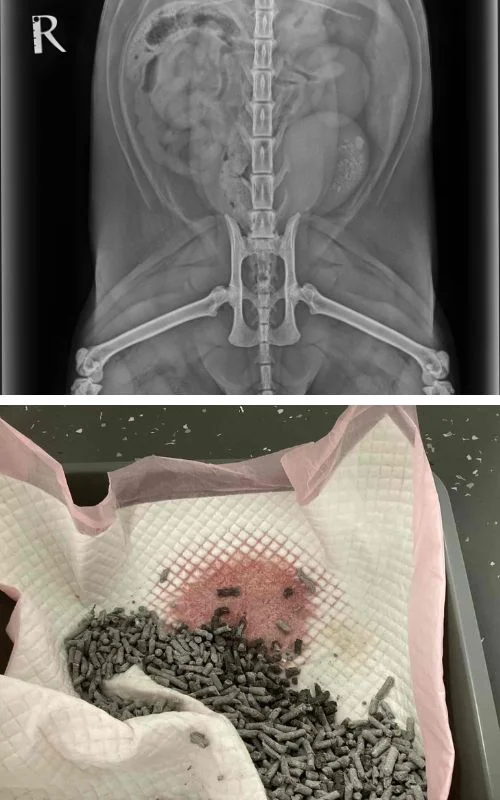

Hector was brought to CSS after experiencing persistent blood in his urine. X-rays revealed numerous calcium oxalate stones in his bladder. Unfortunately, these types of stones cannot be dissolved through dietary changes, making surgery the best option for treatment.

Dr Lincoln Chau performed a cystotomy, surgically opening Hector’s bladder to remove the stones. His follow-up care was overseen by Dr Rachel Korman and her team of nurses, who ensured a smooth recovery after the surgery.